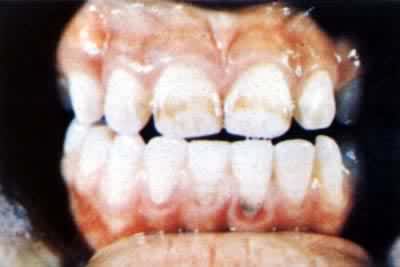

也叫氟斑釉或氟牙症。中国1981年《地方性氟中毒防治工作标准》(试行)规定,生活于高氟区(饮水中含氟量大于1毫克/升或食物中含氟量高的地区)的居民,牙齿出现斑釉即诊断为氟斑牙。出生于高氟区的8~15岁儿童,如氟斑牙患病率在30%以上,即可定为地方性氟中毒地区。氟斑牙可分为白垩型(牙面无光泽,粗糙似粉笔)、着色型(牙面呈微黄、黄褐或黑褐色)和缺损型(牙釉质损坏脱落呈斑点状或呈黑褐色斑块并有花斑样缺损)。轻度患者须在良好光线下仔细辨认才能查出。重度患者对面谈话即可判明。恒齿在生长发育中易得氟斑牙,钙化完全后即不再受损害。(见彩图)